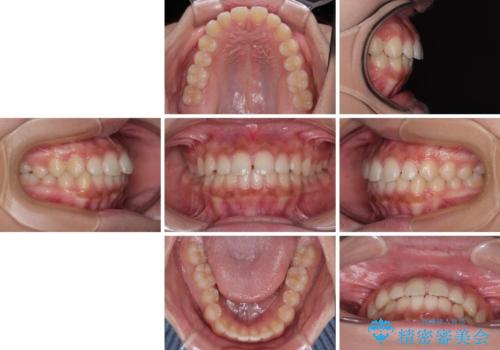

- 前歯の隙間を気にして来院された患者様です。

口元の突出感があり、小臼歯4本を抜歯して口元を引っ込める矯正治療も提案しましたが、本人は口元の突出感は気になっていないとのことで、インビザラインにて隙間やデコボコを改善することとしました。

軽度の歯列不正であったため、廉価版のインビザライン・モデレートパッケージにて治療を終えることができました。